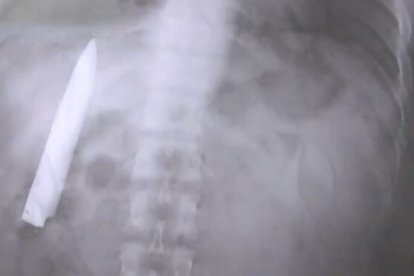

Filipino descubre un cuchillo en sus entrañas 14 meses después de ser apuñalado Redacción Extra Digital